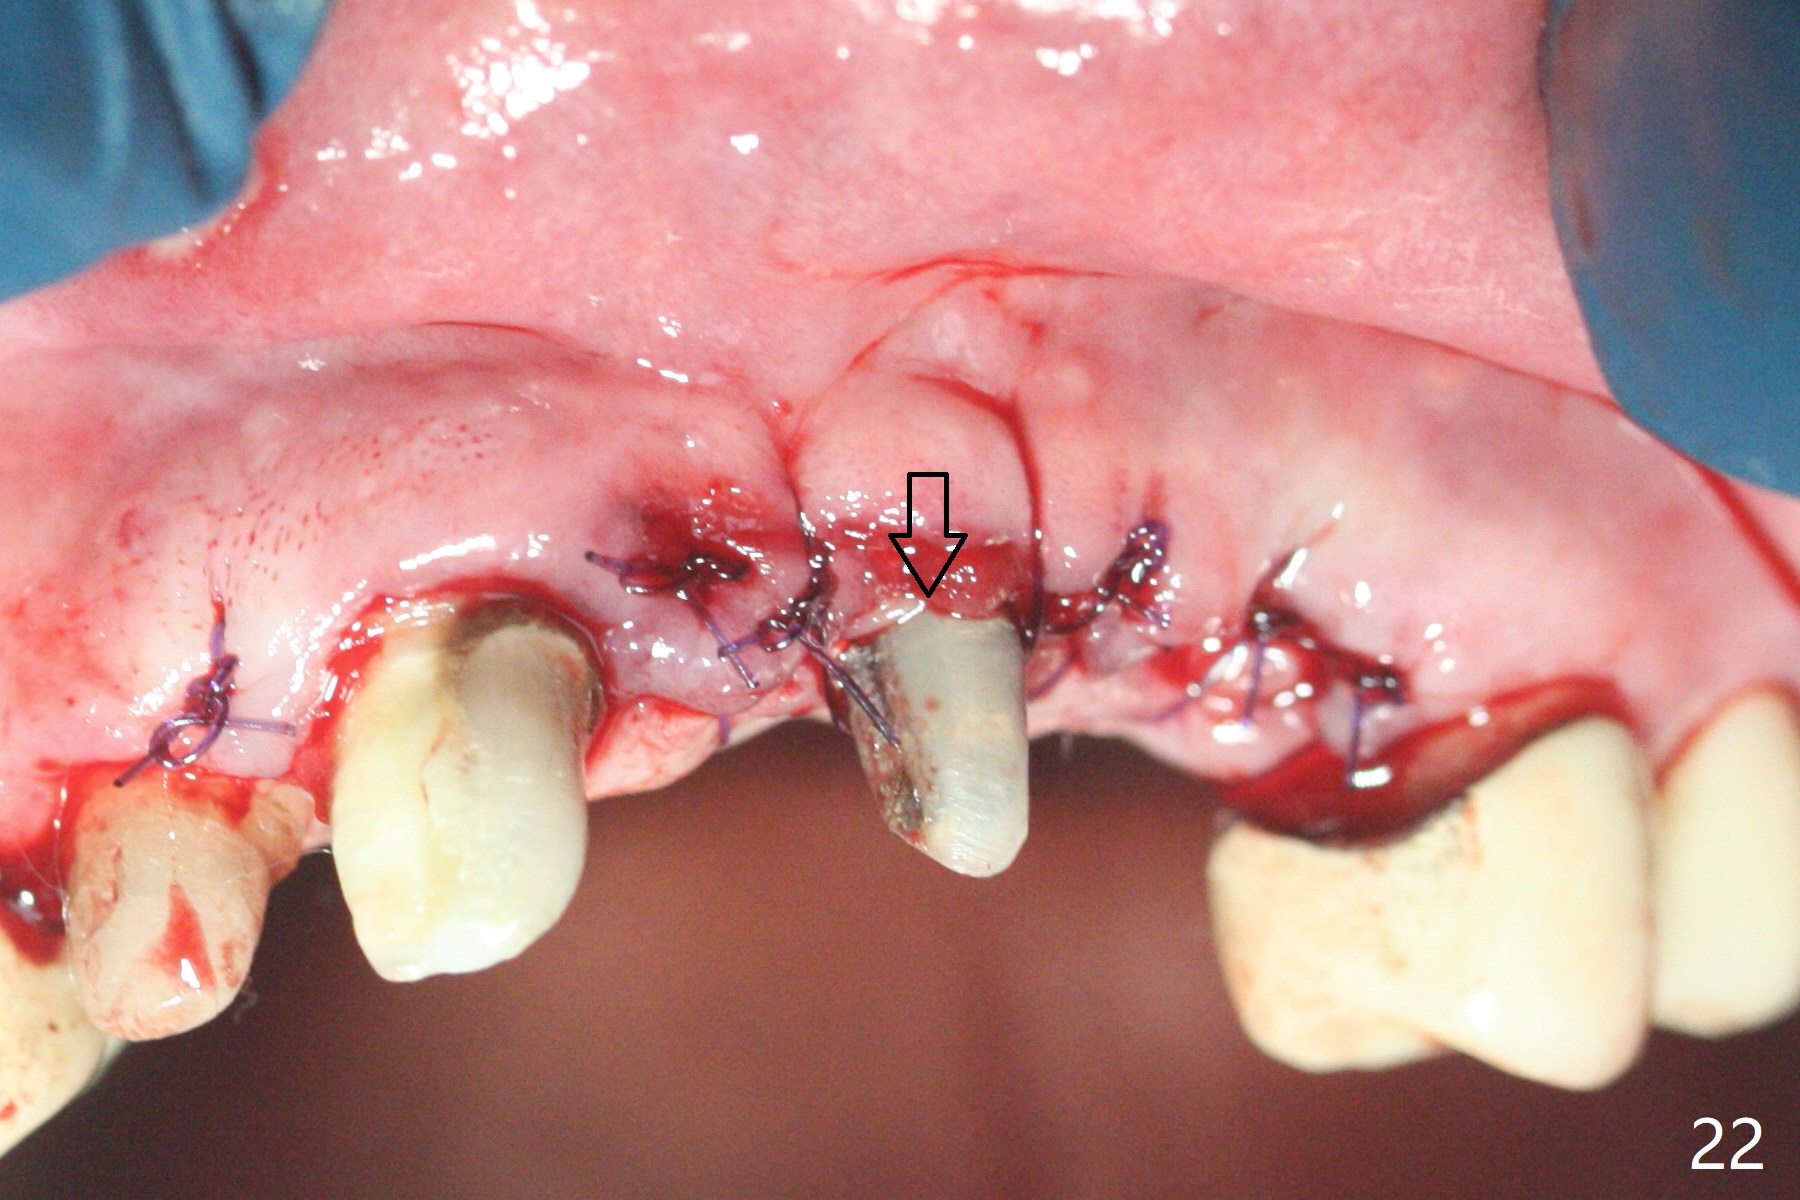

The mesiobuccal margin at #8 is redefined 4 weeks postop (Fig.14) so that the cervical end of the temporary crown is able to move mesially (Fig.13). The most coronal portion of the bone graft at #11 begins to be detached (*). The mesial portion of the abutment at #10 will be removed (curved white line) in the following week. After removing the most coronal portion of detaching bone graft at #11, acrylic is added to form a concave pontic (Fig.15 ^). With removal of the mesial portion of the abutment at #10, the retainer is moved distal (>). Pontics form at UL1 and 3 two months postop (Fig.16 *), while there is buccal atrophy at UL1,2 (Fig.17). 术后3个月植牙区牙龈形态良好(图十八),即将暴露,放置愈合基台。图十九是在右上1根管治疗时(基台放置后五天)拍摄。左上3术后3个月3个星期,1,2唇侧塌陷(图二十)。叶状植体处牙槽嵴往根尖萎缩(图二十一:^)。尽管做了松弛切口,放入事先预备的粘性骨粉后,几乎没有空间放置结缔组织移植物,恰好还没有取。放置PRF膜后,使用4-0 Monoglyc缝线缝合。牙龈似乎冠方移位(图二十二:箭头)。植骨后,唇侧仿佛饱满多了(图二十三:*)。骨粉放置于左上1,2唇侧和牙槽嵴(图二十四:*,与之前(图十九)对比)。后者有助于牙龈冠方移位,而前者有助于增加唇侧饱满度。植骨术后两周唇侧仍饱满(图二十五,六)。植骨后四个月牙冠粘固,两个月后,病人抱怨10号牙左右食物坎塞(图二十七),9/10牙冠撤除,10基台边缘加深,重做临时牙冠,同时增加9凹陷(pontic)。一个月后,9/10临时牙冠修整两次,11永久性牙冠撤除,也制备临时牙冠,外形明显改善(图二十八)。